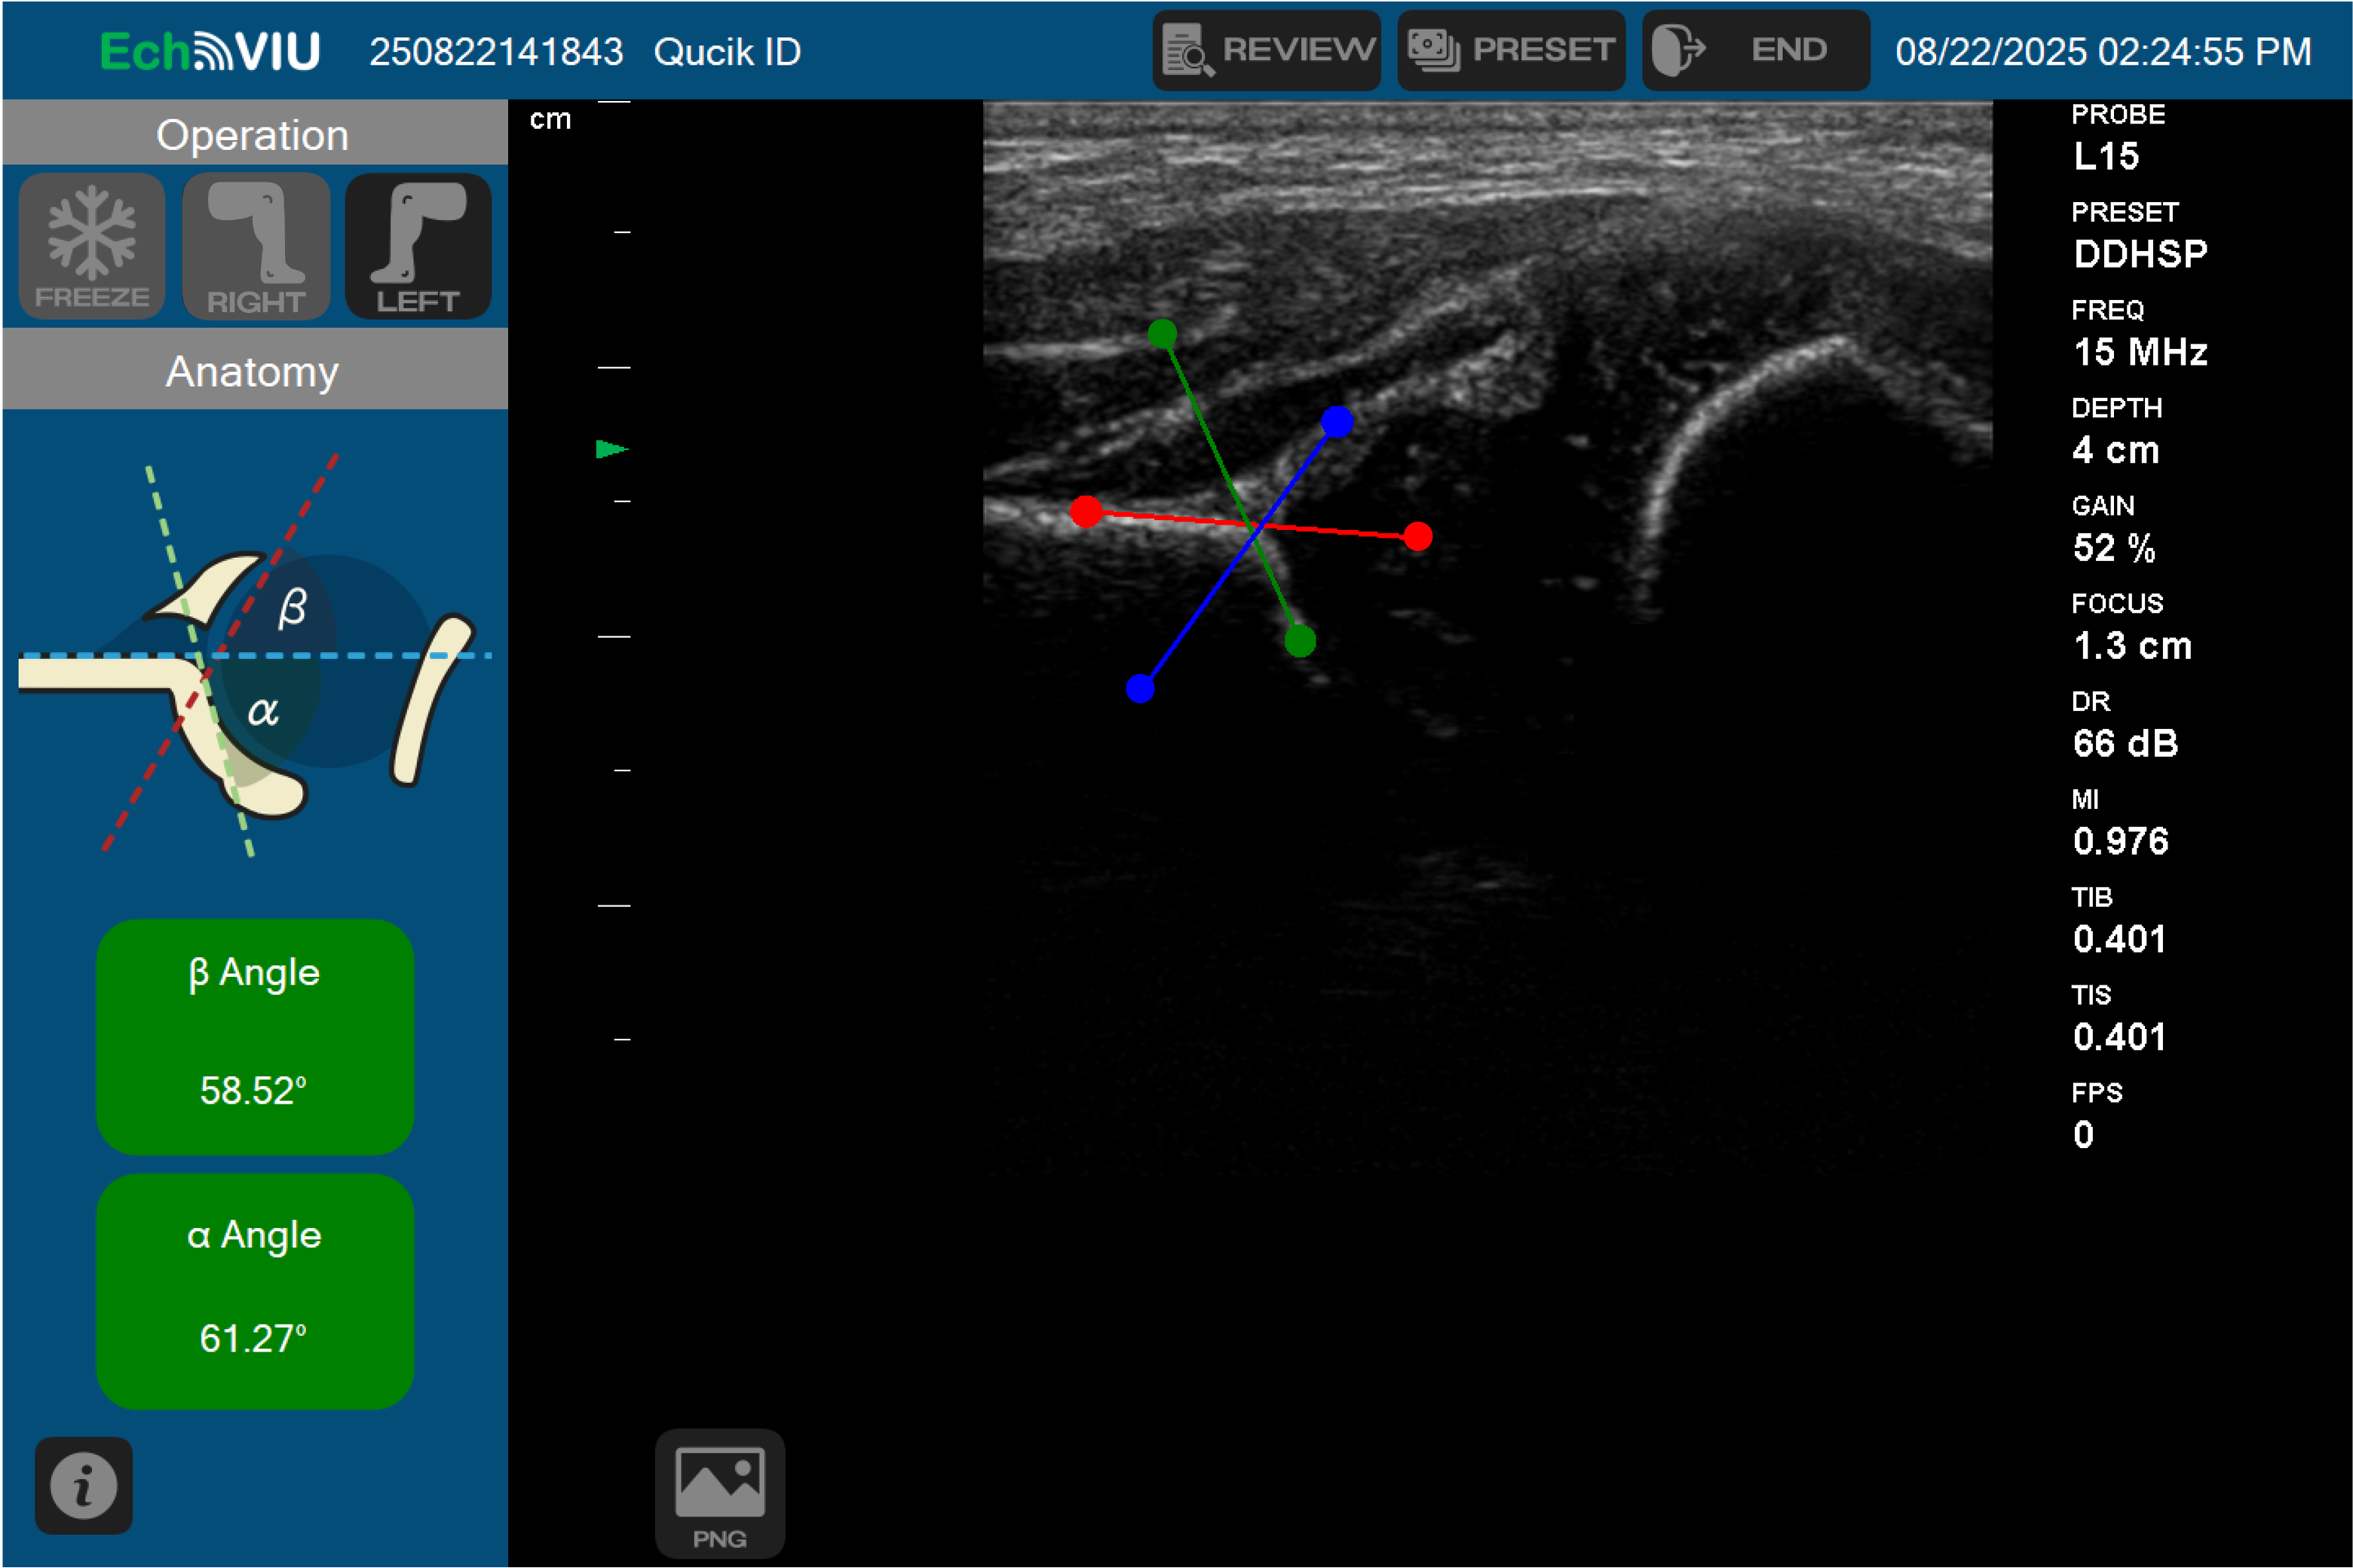

脂肪肝/肝纖維化AI輔助診斷、新生兒髖關節角度AI自動偵測

本系統透過RF訊號演算法搭配AI即時推論技術,進行非酒精性脂肪性肝炎(NAFLD)偵測,量測時間僅需10秒,即可顯示肝臟病灶影像,同時可提供影像輔助定位、局部病變結果。此外,系統可將檢測結果之嚴重程度分為四個階段,醫師可藉由分數分級進行輔助診斷。本公司透過與Intel、遠傳電信、國家衛生研究院、長庚紀念醫院合作,將AI超音波技術佈署於Intel OpenFL(Open Federated Learning),結合遠傳電信的遠距醫療平台,為醫生和患者提供視訊門診對話,使NAFLD脂肪肝篩檢更加容易。 過去醫師以理學檢測確認新生兒髖關節有無異常,檢測一位新生兒平均所需時間為15-20分鐘,本公司與林口長庚紀念醫院骨科團隊合作,研發之AI即時推論超音波系統可將篩檢流程縮短至30秒,除運算快速、可針對超音波影像進行自動判讀,亦可量測髖關節角度,以判斷新生兒髖關節是否異常,避免錯過最佳黃金治療期。